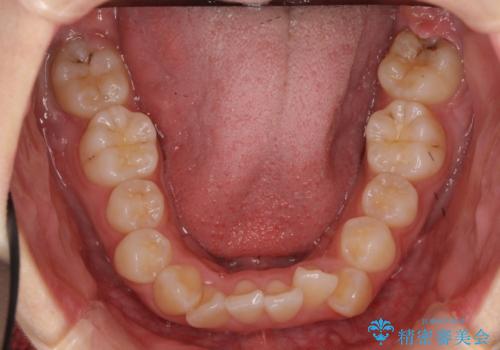

- 前歯のがたがたを主訴に来院。

口元も下げたいとのことでした。

成人式の時に前歯が下がって、揃った状態で写真を撮ることができ、大変喜んでおられました。